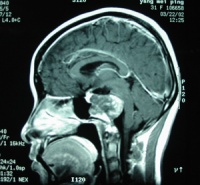

核磁共振成像(MRI)

另外 除了医疗上面的用途之外,影像学结合其他学术领域,譬如认知心理学(cognitive psychology)、语言学(linguistics)、教育学(education)、社会学(sociology)等,可以让研究人员探索人类在进行认知行为时的大脑活动,这样的研究已经逐渐成形,学术界称之为认知神经科学(cognitive neuroscience)。